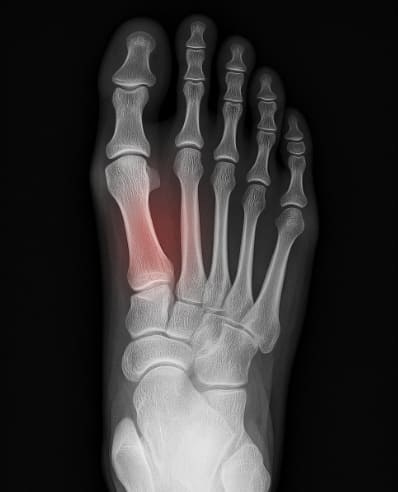

③ 피로골절

과도한 걷기, 달리기, 트레킹, 군화 착용 등의 반복적인 하중이 발등 뼈에 미세한 균열을 만들어 피로골절이 발생할 수 있습니다. 보통 X-ray 초기 검사에서는 잘 드러나지 않아 놓치기 쉽지만, 통증이 점차 심해지며 오래 지속되는 경우 피로골절을 의심해야 합니다.